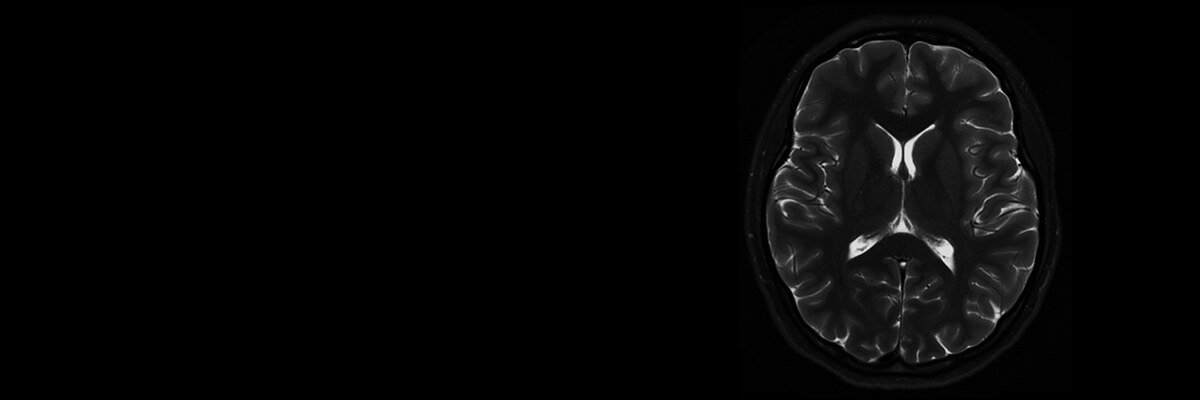

Make no substitutes for image quality

Clearly consistent images

Simply better compared to conventional coil technology.